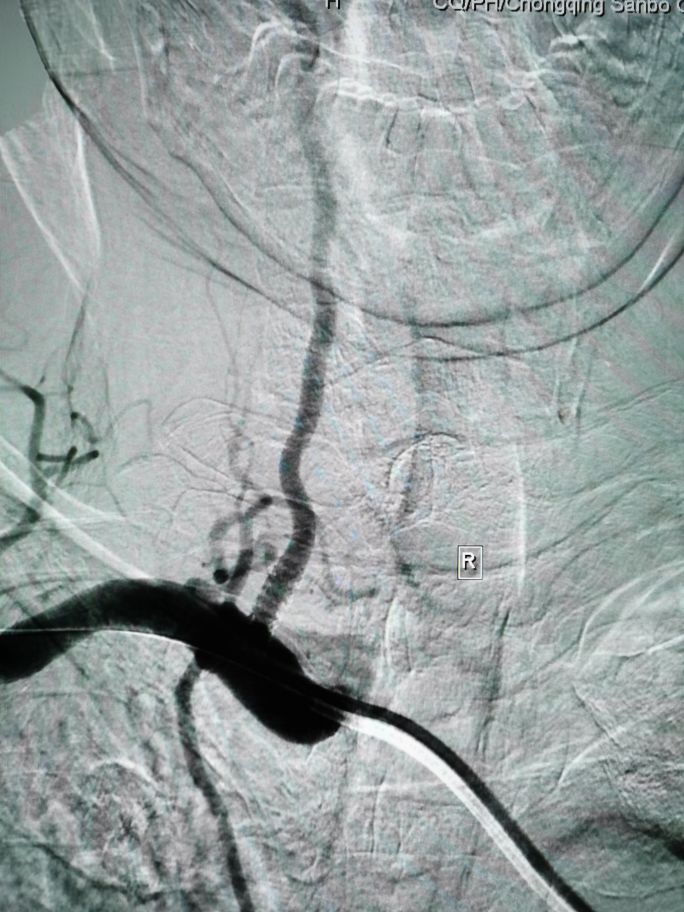

造影显示右侧椎动脉为优势椎,起始部重度狭窄!左侧椎动脉起始部闭塞!

改善后循环供血最有效的办法就是打开右侧椎动脉,改善供血!造影术中,与患者家属沟通后,给予右侧椎动脉支架置入!

术后,患者后循环(椎动脉,基地动脉,大脑后动脉,小脑上动脉,小脑前下动脉,小脑后下动脉)血供明显改善!